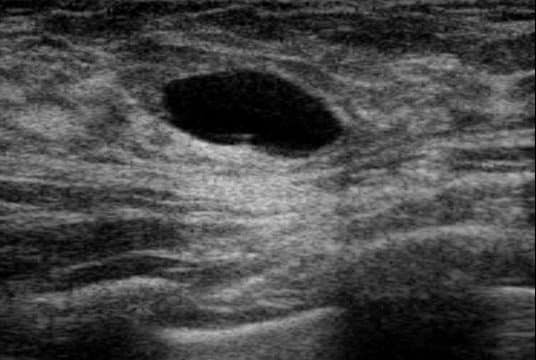

discuss other types of breast cysts

A

can be due to blocked duct causing a lobule to become distended.

can be one or multiple

distinct smooth masses.

halo sign

can be left or drained once identified.

if on aspiration there is no blood and the lump disappears then that is a good sign.